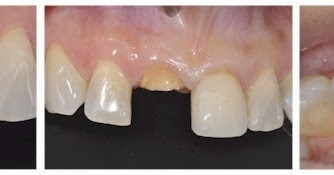

Restauracion Clinico Quirurgica Integral En Fractura Complicada De Corona Y Raiz Del Tercio Medio En Visita Unica

scielo.sld.cu